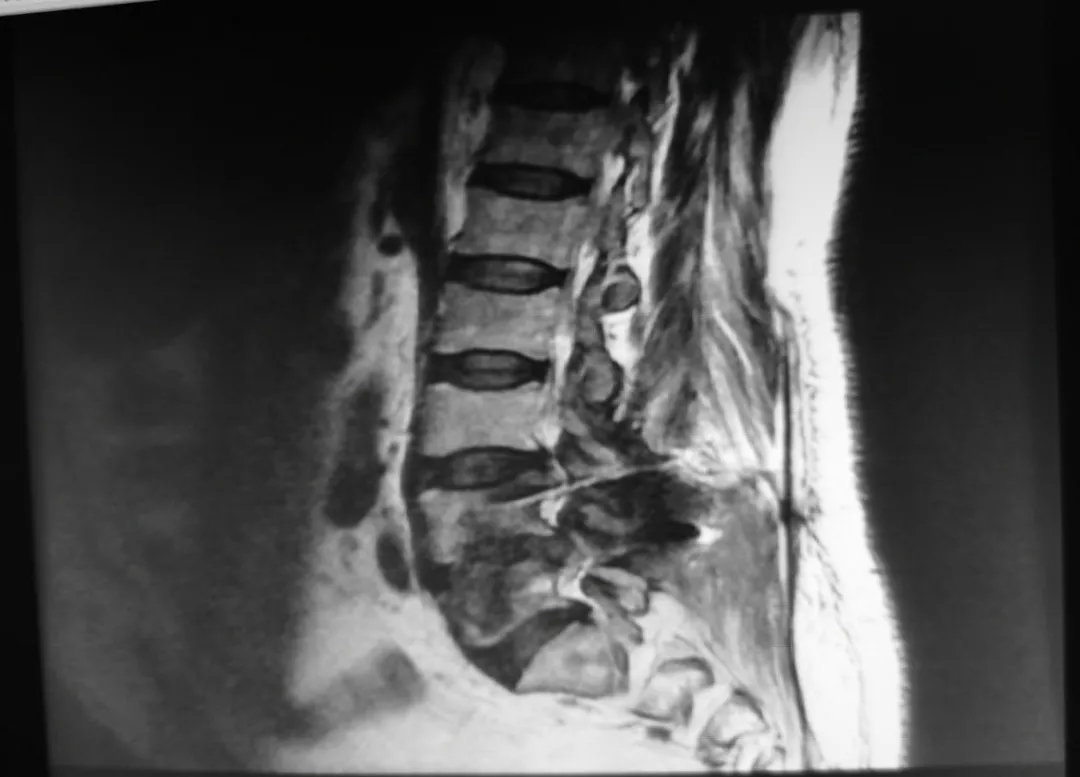

腰椎内固定术后影像:CT可见椎体多个低密度灶。

▲MR

骨卫士专家委员会副主席杨述华教授肯定了陈仲教授的诊断及治疗方案。他表示,此病例是一个迟发性的晚期的深部感染,病例的临床症状及影像学有明显的感染迹象,同时C反应蛋白高,陈仲教授通过椎间孔镜取出肉芽组织,进一步证实了病例是感染型。临床上我们提倡能吃药的不打针,能打针的不开刀,能开小刀的不开大刀。陈仲教授的治疗方法很合理,对患者没有造成大的创伤。因为这个患者感染比较严重,涉及到椎体,可能会出现一些或轻或重的疼痛。如果患者出现重度或难以忍受的疼痛,可以选择进一步手术。手术方案可以考虑将后侧螺钉撤掉,前入路做椎体内固定。